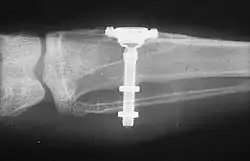

The phenomenon of osseointegration was first described by Bothe et al. in 1940 and later by Leventhal et al. in 1951.[11][12] Brånemark's studies, and his subsequent coining of the phrase osseointegration, occurred a year after Leventhal during vital microscopy studies in rabbits using titanium optic chambers. He and his team found that titanium oculars placed into the lower leg bones of rabbits could not be removed from the bones after a period of healing (see photo at right).[13] He then developed and tested a type of dental implant utilizing pure titanium screws, which he termed fixtures.[9][14]